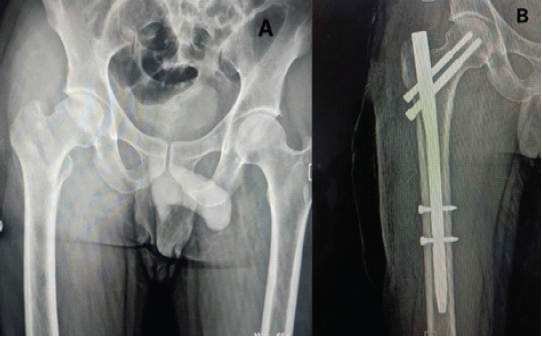

A 30-year-old male patient with TYPE 31-A1.2 pertrochanteric femur fracture of the right side (Fig. 1).

Figure 1: (a) Pre-operative anterior-posterior (A-P) view X-ray showing TYPE 31-A1.2 pertrochanteric femur fracture of the right side. (b) Post-operative A-P view X-ray showing pertrochanteric femur fracture fixed with short proximal femur nail.